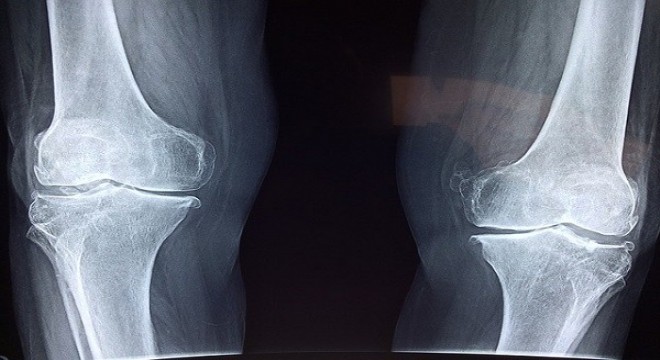

Diz kapağında eklem kireçlenmesine dikkat

Çömelme ya da merdiven inip çıkma esnasında dizlerinizden gelen sesle ...